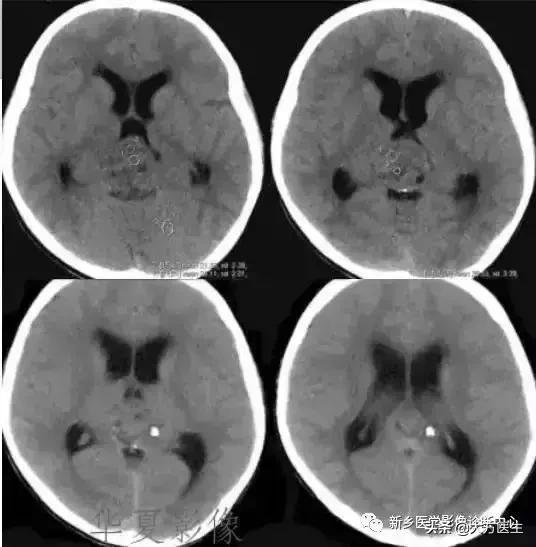

3、颅咽管瘤

多见于20岁以下,常有内分泌代谢障碍及视觉障碍,部分可有颅高压表现。

X:可见鞍区钙化,蝶鞍异常扩大及颅高压征象。CT:见囊实性肿块,囊壁斑块、蛋壳样钙化。MR:T1高等低混杂信号,T2为高信号。